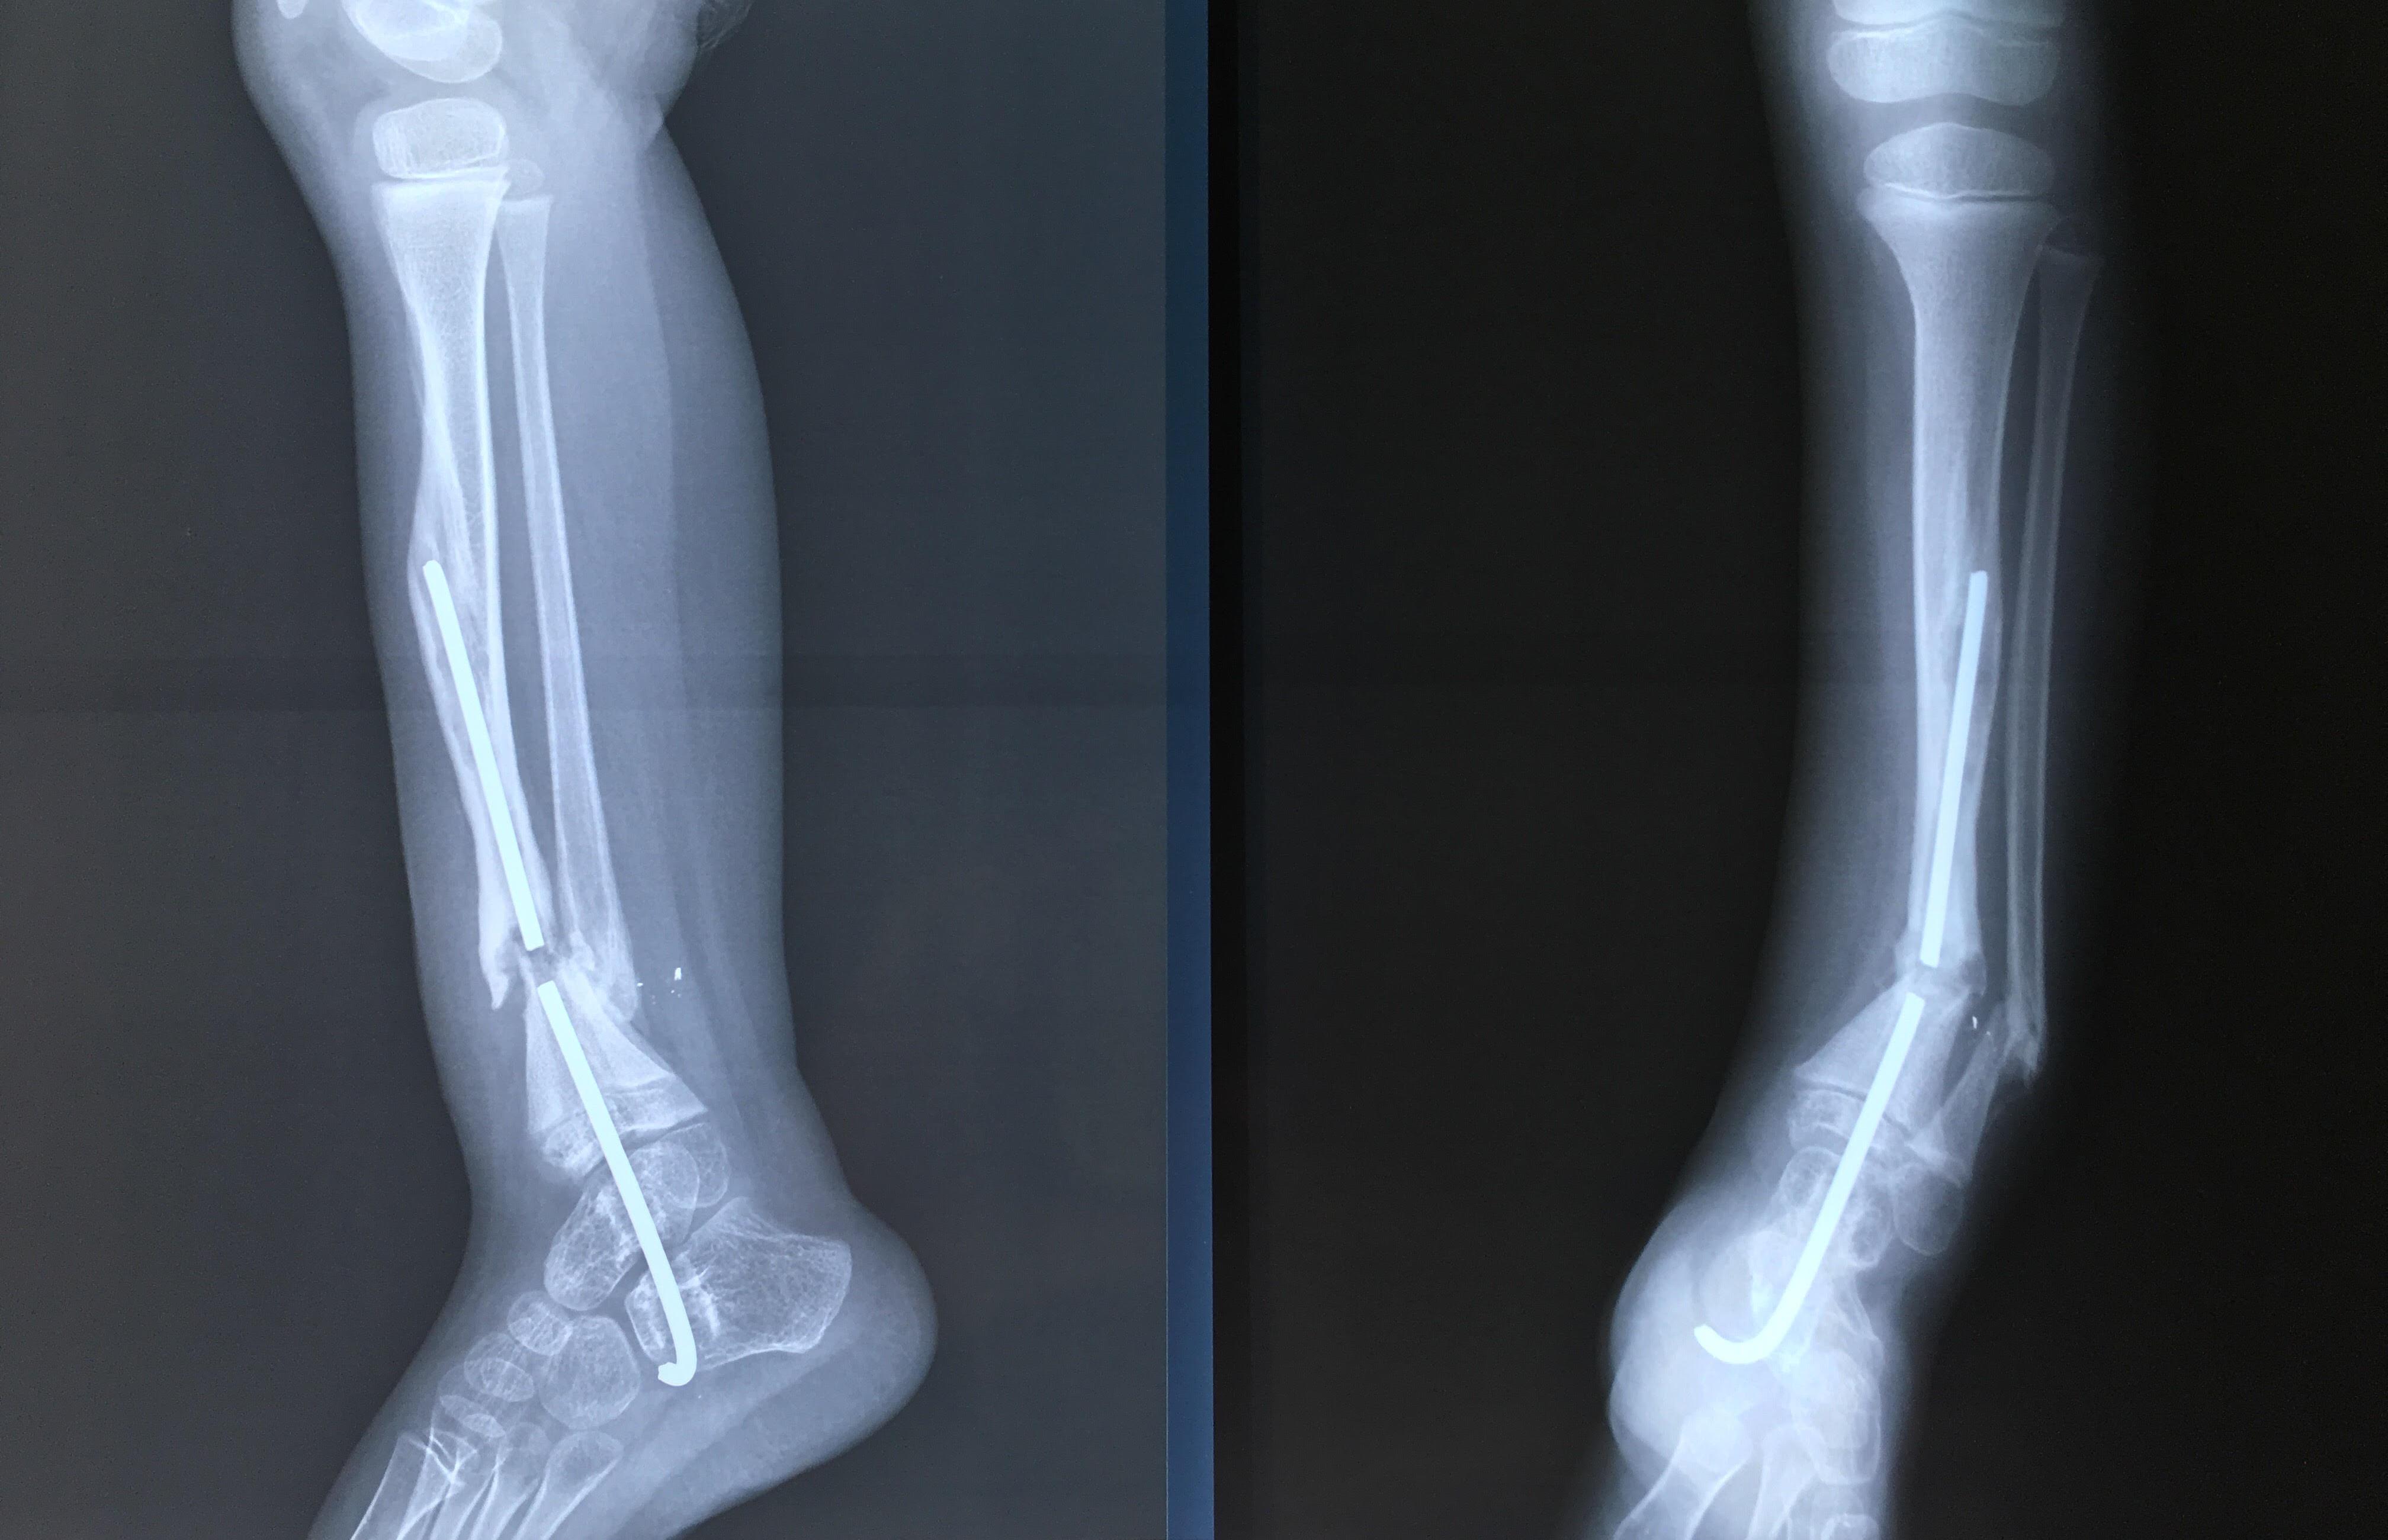

Phẫu thuật thành công ca bệnh hiếm gặp...khớp giả bẩm sinh xương chày

26/06/2019 17:00

Đã xem: 3461

Bệnh viện Chấn thương- Chỉnh hình Nghệ An, vừa phẫu thuật thành công cho bệnh nhi khớp giả bẩm sinh xương chày